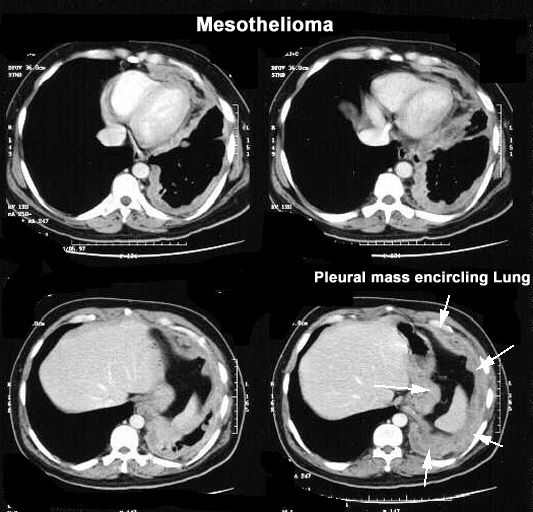

CT showing pleural mass encircling lung.

Mesothelioma